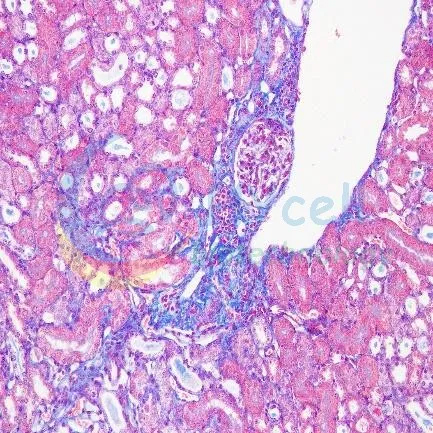

Masson染色

| 正常组 | 模型组 |

Masson染色结果:与正常组相比,模型组肾小管结构紊乱、管壁变薄,肾间质增宽,肾小球及间质出现纤维组织增生,有蓝色胶原纤维沉积。